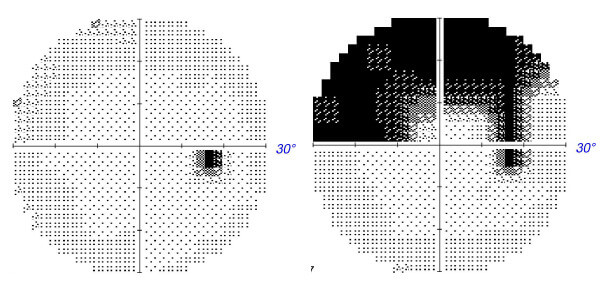

(consistent with atrophic changes) RNFL superior in the left eye. The patient denied pain on eye movement, headache, or other neurological or systemic symptoms. In addition to the previously diagnosed NAION OS, the patient’s medical history included hypertension, hyperlipidemia, gastroesophageal reflux disease (GERD), anxiety, obesity, prediabetes, and untreated obstructive sleep apnea (OSA). The patient denied symptoms consistent with arteritic ischemic optic neuropathy (AAION). His active medications included fluoxetine Hcl 20 mg for anxiety, lisinopril 40 mg for hypertension, ranitidine Hcl 150 mg for GERD and diet-controlled prediabetes. A STAT erythrocyte sedimentation rate (ESR), C-reactive protein test (CRP) and complete blood count (CBC) were ordered. The patient was advised that there appeared to be incipient NAION in his right eye. The patient’s PCP was consulted with advice to monitor cardiovascular risk factors, for nocturnal hypotension and obstructive sleep apnea (OSA). Nine days later, the patient reported losing vision above fixation in the right eye with no change to the left. Uncorrected central VA remained 20/20 in each eye. There were new petechial hemorrhages at the inferior disc margin OD and an increase in optic nerve swelling. The increased optic nerve swelling was quantified using OCT (see Figure 2 for baseline and nine day later OCT measurements). Visual field testing showed a new superior altitudinal depression OD and a stable inferior altitudinal loss OS (see Figure 3 for comparison of right eye visual fields taken at baseline and nine days later). The patient was diagnosed with acute phase classic NAION OD and stable atrophic phase NAION OS. The patient was monitored closely over the next weeks as the right eye went through the acute phase of NAION with progressively increasing optic nerve swelling followed by the stable atrophic phase.

Figure 3. HVF 30-2 right eye gray scale taken at baseline (left) and nine days later (right). The patient was initially diagnosed with “incipient” NAION that converted to “classic” NAION.